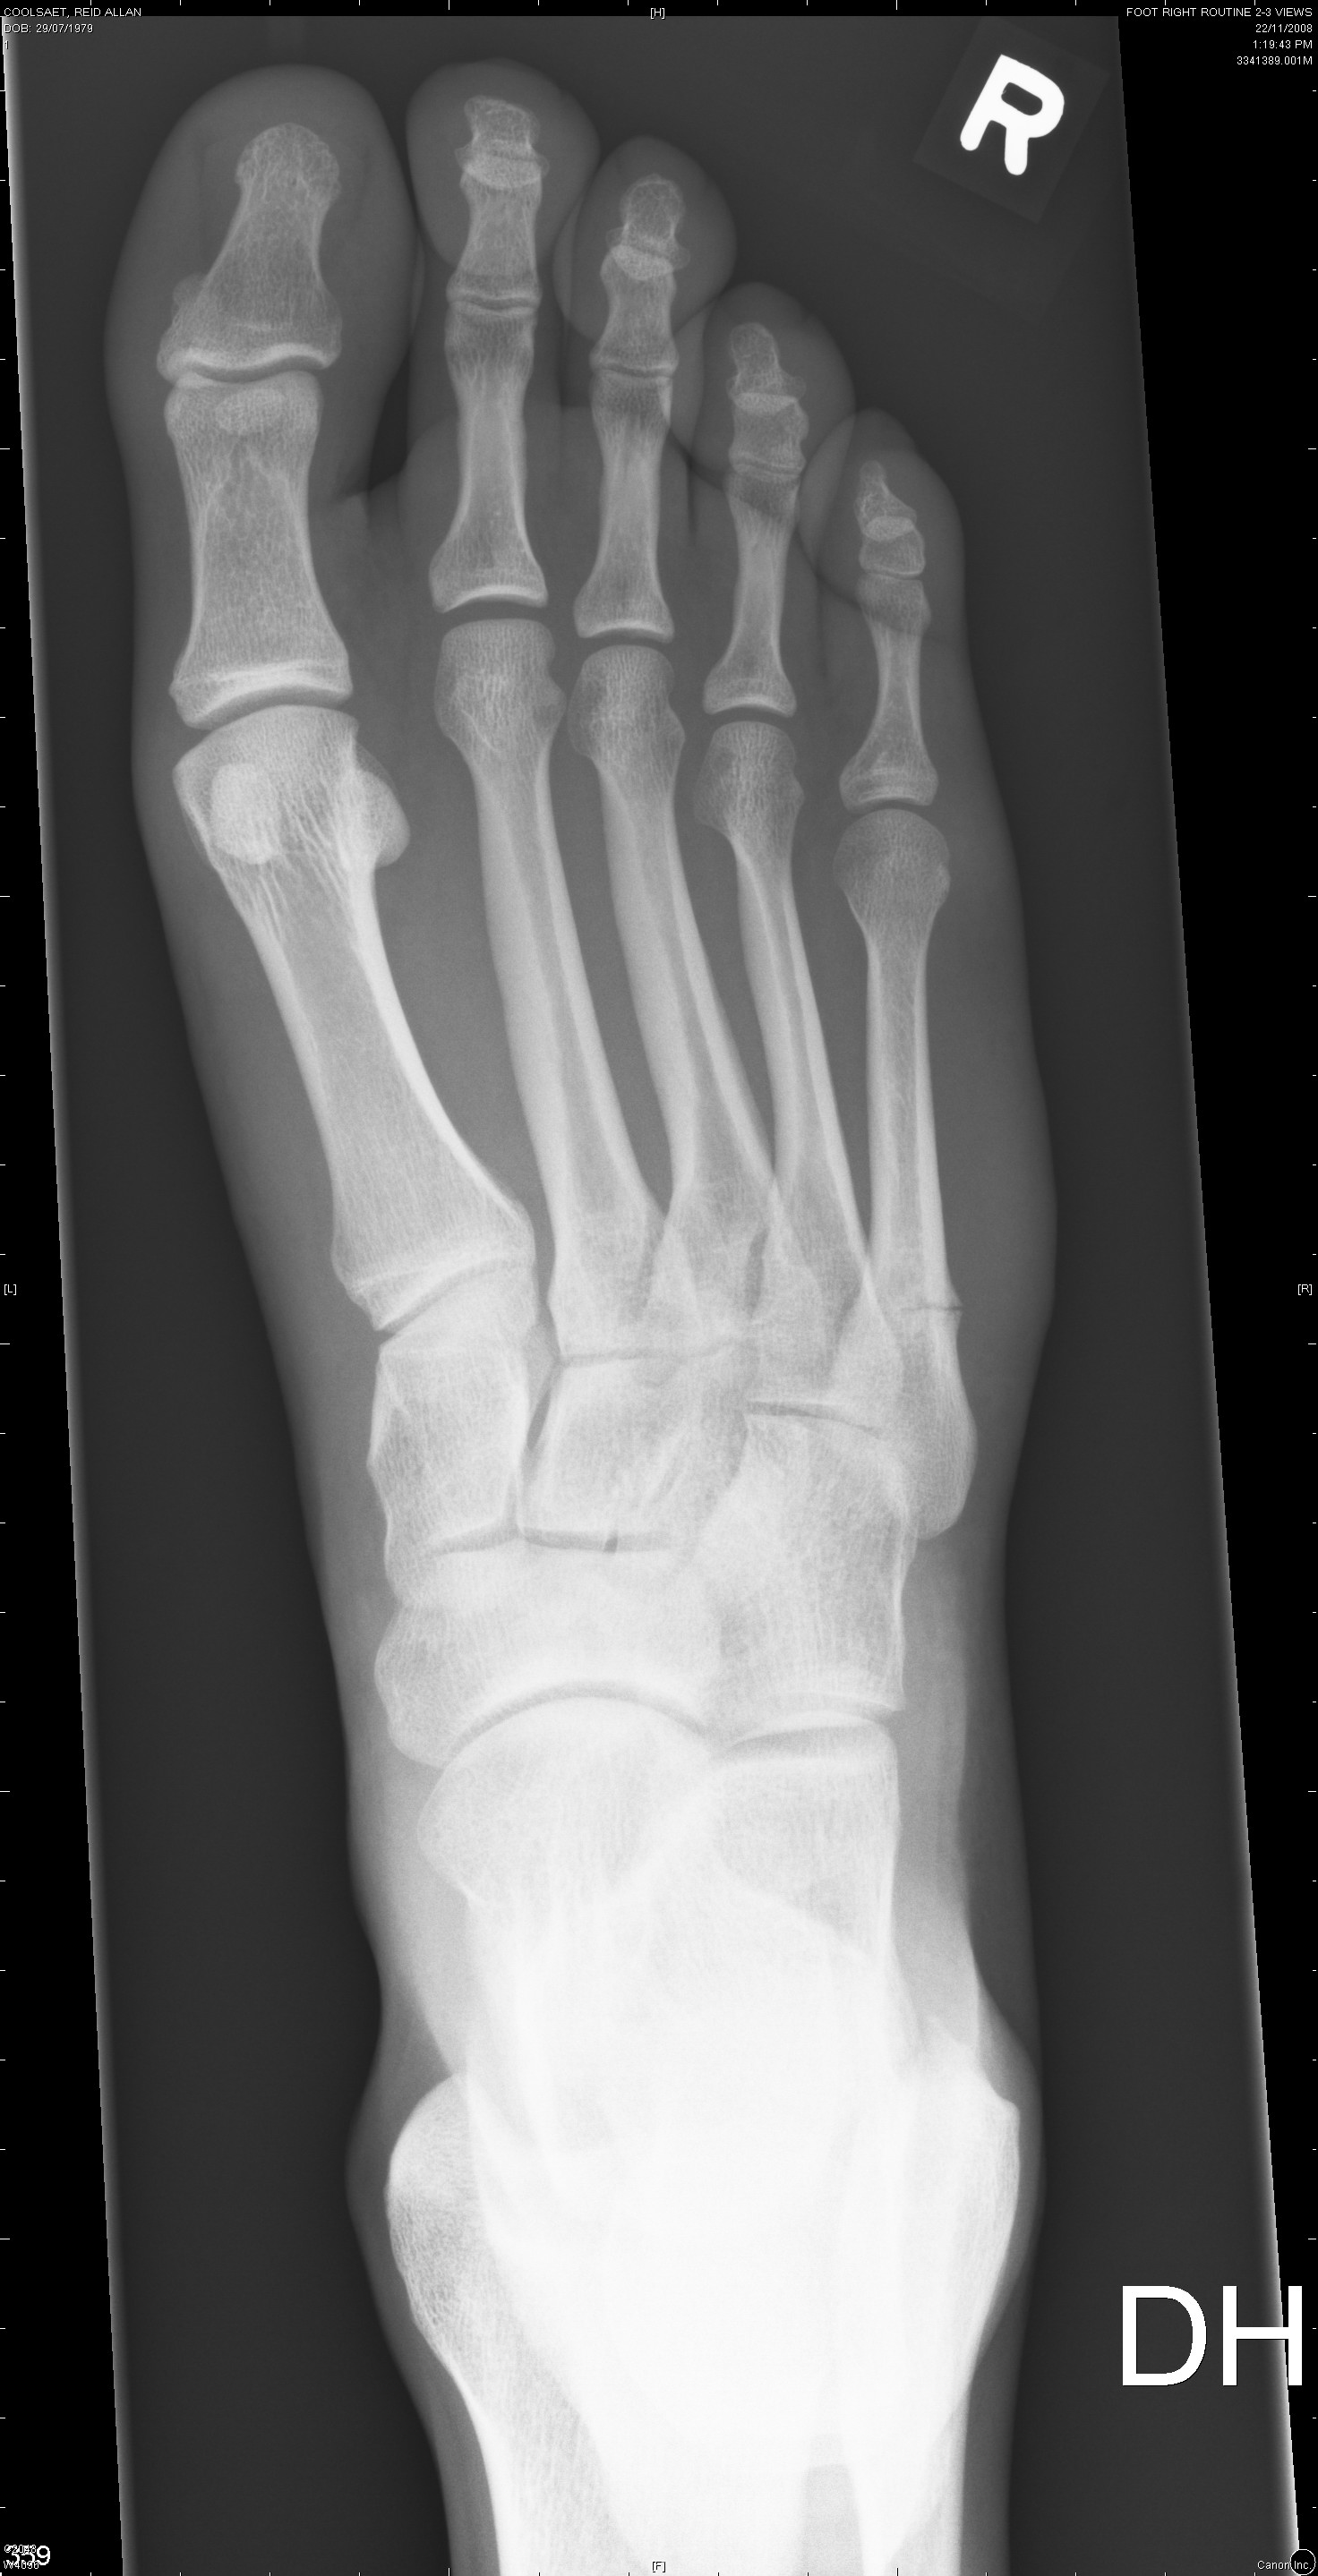

The first two are from November 6th and the last two are from November 22nd.

Nov. 22